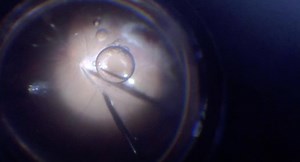

- Retinal Detachment

Surgery - Vitreous

Detachment - Scleral

Buckle - Retinal